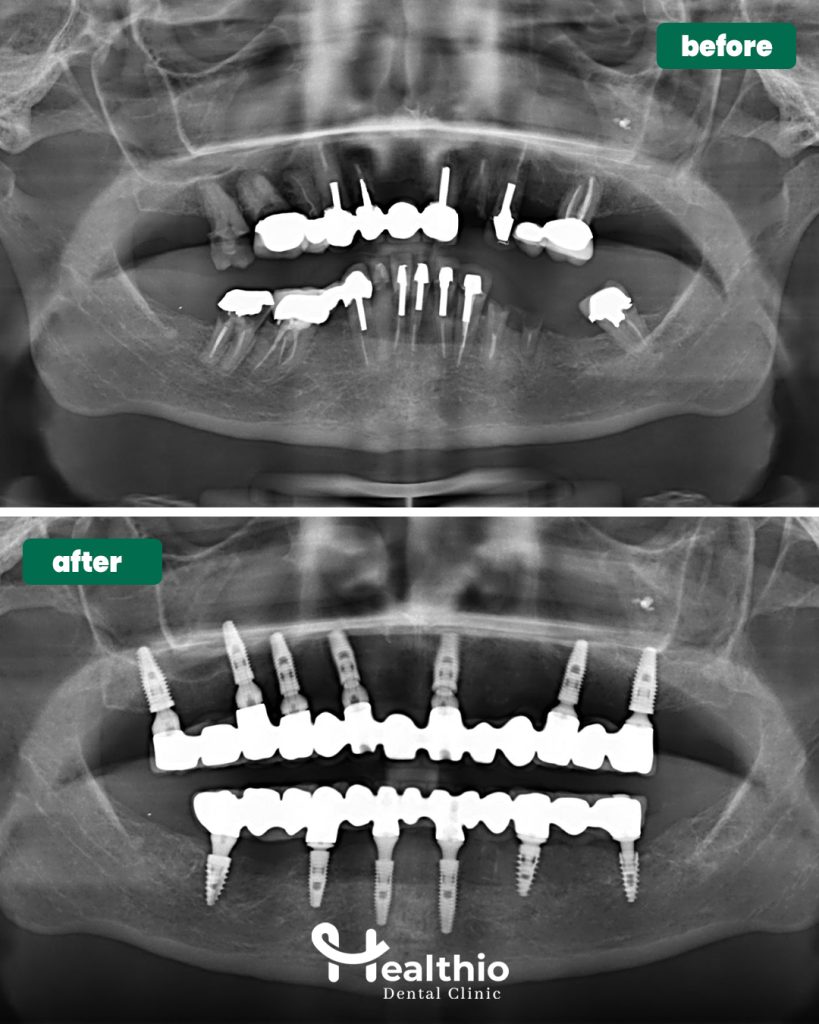

Full Mouth Dental Implants Turkey Package Deals are a comprehensive restorative solution designed to replace an entire arch—or both arches—of teeth using a fixed, implant-supported prosthesis. Unlike removable dentures, implants are anchored into the jawbone, providing exceptional stability, function, and a natural appearance.

- All-on-4 dental implants

- All-on-6 dental implants

- Customized full arch implant bridges